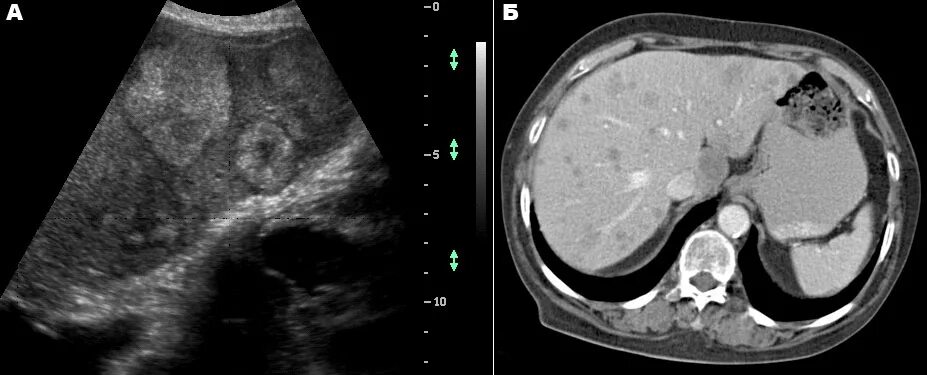

Метастазы в печени на узи